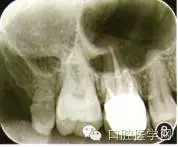

(1)基本情況:患者男性,34歲,主訴:右上后牙自發(fā)性陣痛3 d。2個(gè)月前右上后牙區(qū)出現(xiàn)冷刺激痛,近3天出現(xiàn)自發(fā)痛,疼痛放散至同側(cè)頭面部,夜間加重,疼痛不能定位?;颊叻裾J(rèn)全身系統(tǒng)性疾病,否認(rèn)藥物過(guò)敏史??谇粰z查示6睡中鄰胎面齲壞,可探及穿髓點(diǎn),探診疼痛明顯,冷熱診疼痛,叩診無(wú)明顯不適,牙齒無(wú)松動(dòng),牙齦無(wú)紅腫。型未發(fā)現(xiàn)異常。根尖x線片示6遠(yuǎn)中鄰駘面透射影已到髓腔,根尖周未見(jiàn)明顯異常(圖1)。診斷:6慢性牙髓炎急性發(fā)作。治療方案:6根管治療術(shù)后全冠修復(fù)。

圖1 6術(shù)前根尖x線片示遠(yuǎn)中鄰耠面深齲及髓(箭頭),根尖周未見(jiàn)明顯陰影